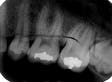

Perhaps the most common error is the overlapping of contacting surfaces (see Radiograph 1). When this occurs, the interpretation of caries is difficult at best. At worst, depending on the degree of overlap, interpretation often becomes virtually impossible.

The overlap is the result of incorrect horizontal angulation. With the paralleling technique, improper film-holder placement can be the cause. A simple adjustment in the film-holder`s position places it parallel to the facial surfaces of the teeth being exposed.

But the overlap can also be the result of errors in the angle of projection either mesiodistally or distomesially. When the horizontal plane projection is directed from mesial to distal, the resulting larger areas of overlap appear in the posterior portion of the film. Conversely, if the larger overlap appears in the anterior portion of the film, the horizontal plane of projection was directed distal to mesial.

To change this, place the film parallel to an imaginary line that is parallel to the facial surfaces of the teeth. The plane of the positioning indicating device/cone (PID) should then be parallel to this line and the film together. To determine the degree of overlap, use this general rule: If the overlap covers more than one-half of the enamel`s width, the degree of incipient decay and etchings are difficult to determine, and major technique problems need to be addressed.